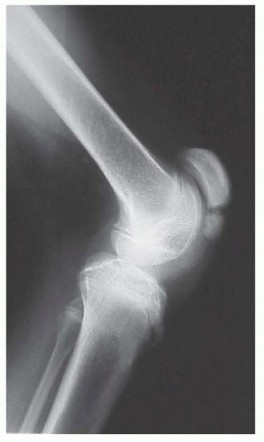

Surgical Management of Blount Disease DEFINITION Blount disease, also known as idiopathic tibia vara and oste…